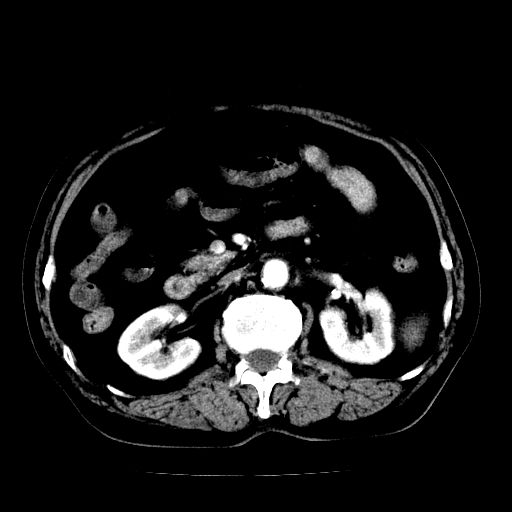

男,71岁,皮肤黄染四天。

胆管癌并肝内外胆管扩张。

支持考虑胆总管癌并肝内外胆管扩张。 局部应薄扫。心包钙化。